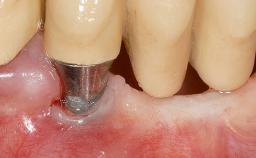

Periodontal Plastic Surgery and Prosthetic Procedures to Treat Peri-Implant Soft-Tissue Dehiscences

A 30-year-old woman was referred by her general dentist for evaluation of an esthetic complication related to previous implant treatment for congenitally missing maxillary lateral incisors. The patient’s chief complaint was the inadequate esthetic appearance of her smile. The case demonstrates the use of a combined approach to achieve optimal results. Two different flap designs - a tunnel technique and a coronally advanced flap - are employed based on the surgical objectives for the affected site.

Soft Tissue Grafting Yes

Abutment Type Standard